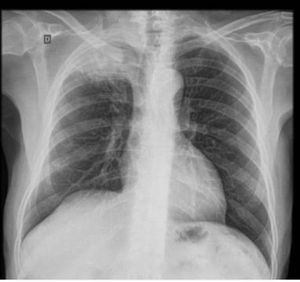

Wt will be ur diagnose....

Pancoast tumor

right upper lobe Atlectasis🤔

Carcinoma apex of the lung (pancoast tumor)